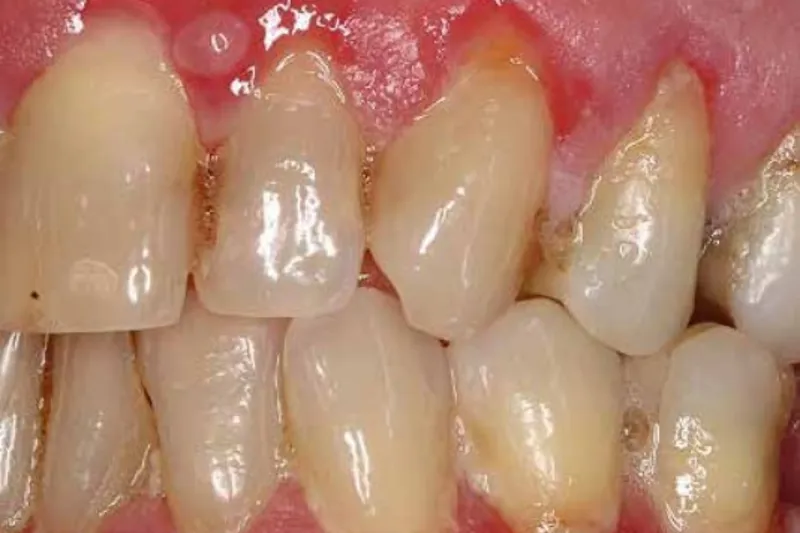

Blæredannelse i mundslimhinden kan forekomme af mange forskellige årsager. Den hyppigste årsag hertil er virusinfektioner, herunder herpes simplex- og varicella zoster-virusinfektioner. I disse tilfælde vil blærerne typisk have karakter af vesikler, det vil sige væskeansamlinger på under 5 mm, der typisk optræder i klynger. Blæredannelser i mundslimhinden kan også skyldes visse autoimmune sygdomme, hovedsageligt pemfigus vulgaris og pemfigoid. Blæredannelserne har karakter af bullae, der hurtigt brister og efterlader en eroderet slimhinde, som dækkes af fibrin. Desuden kan blæredannelser opstå som følge af genetiske sygdomme som fx epidermolysis bullosa. Endelig kan blæredannelser udløses som reaktion på fx lægemidler som ved erythema multiforme, der kan optræde i varierende grader. Blæredannende mundslimhindesygdomme er ofte forbundet med smerter og ubehag. I nærværende artikel gennemgås de mest almindelige sygdomme, der manifesterer sig med blæredannelse i mundslimhinden.

Blistering in the oral mucosa may occur due to different reasons. The most frequent cause of blistering in the oral mucosa is viral infections, including herpes simplex and Varicella-Zoster virus infections. Here, the blisters primarily present as vesicles, fluid accumulations of less than 5 mm that appear in clusters. Blisters in the oral mucosa can also be caused by specific autoimmune diseases, mainly pemphigus vulgaris and pemphigoid. The blisters are characterized as bullae, which bursts easily and leave behind an eroded mucous membrane, which is covered by fibrin. A blistering oral mucosal disease is often associated with pain and discomfort. In this article, the most common diseases giving rise to blistering in the oral mucosa are reviewed.